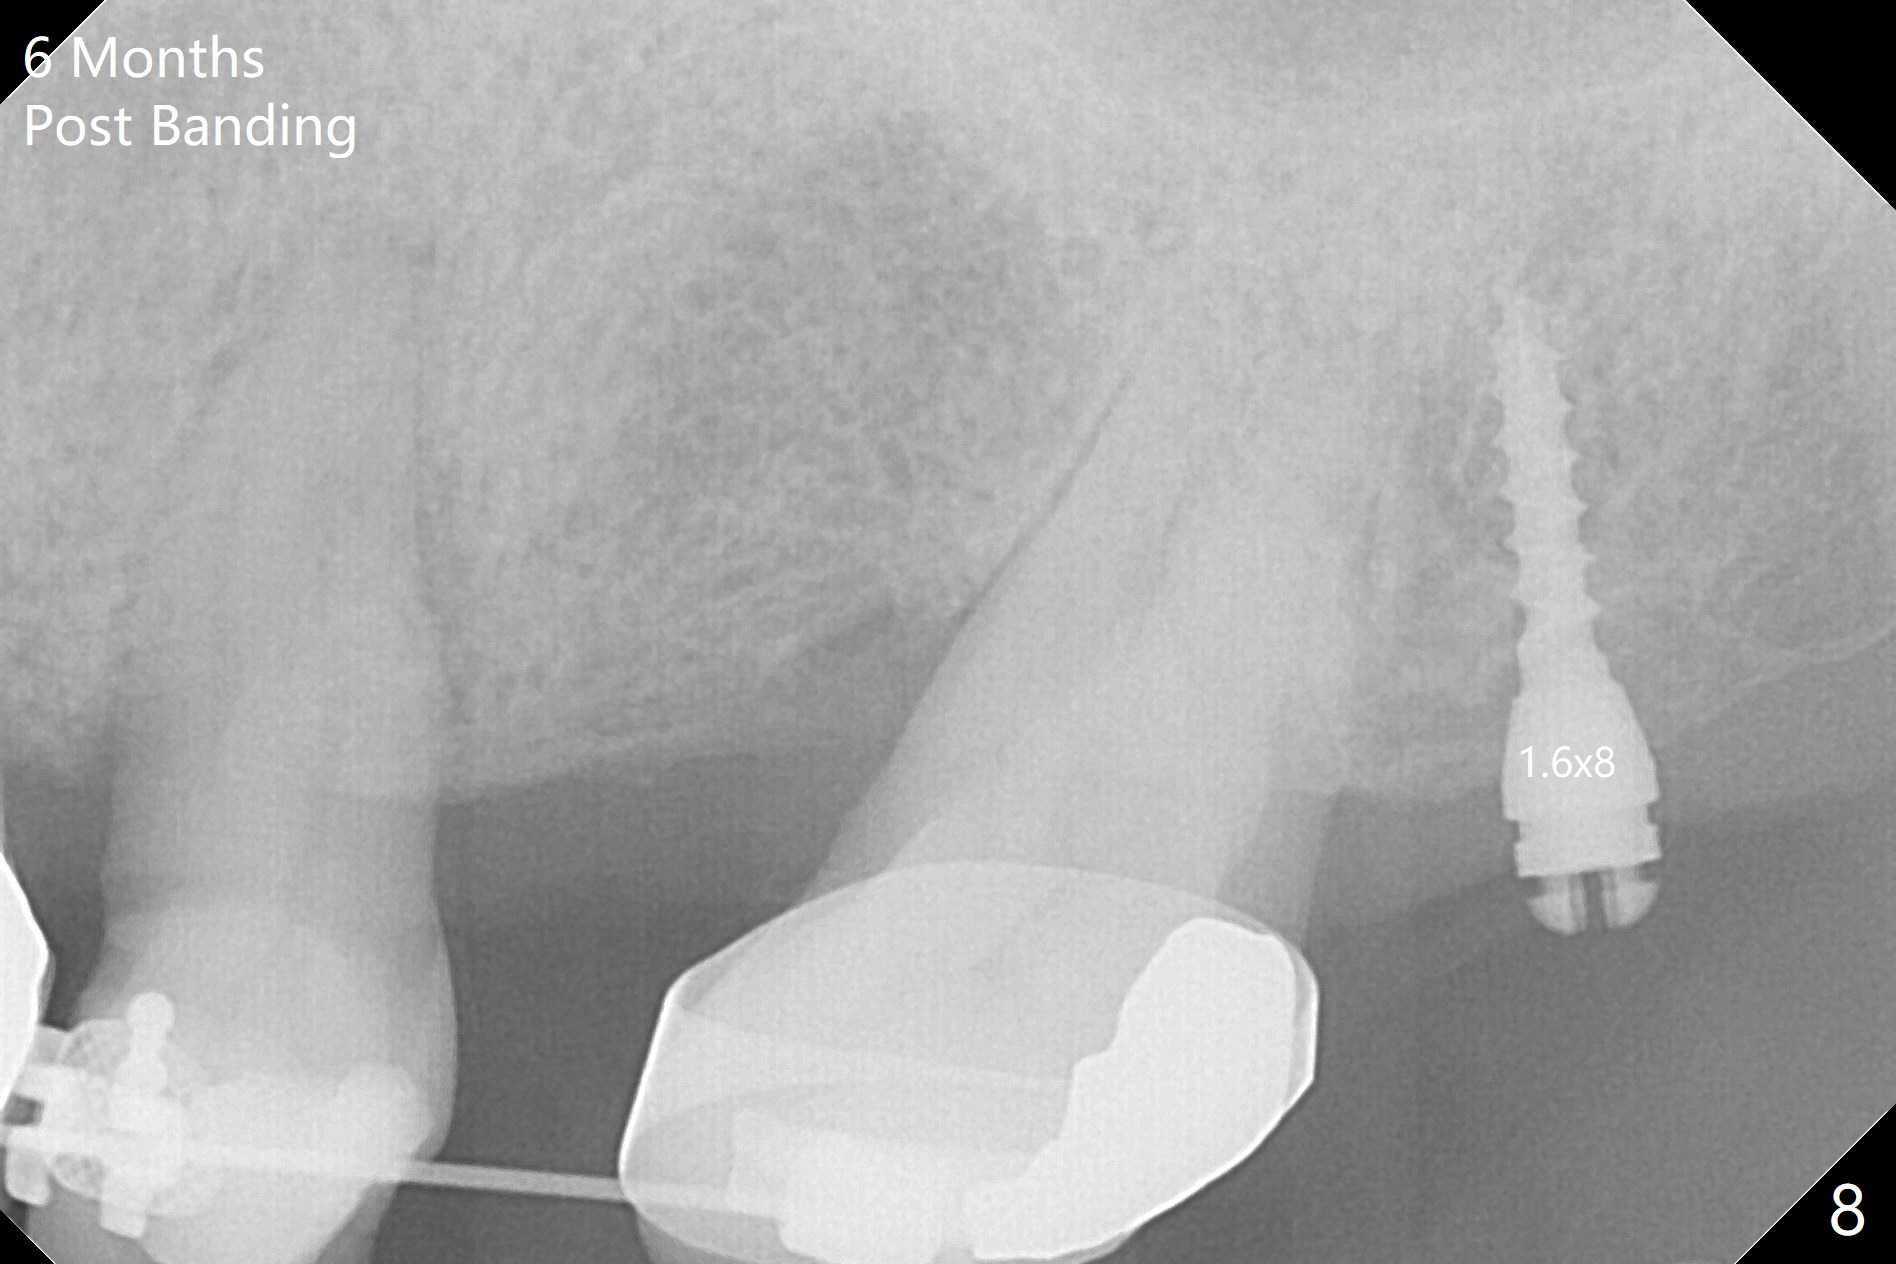

Ultradent Prime and Bond is used bracketing. The bonding system appears to be able to attach the brackets to porcelain crowns at #10 and 12 (Fig.3 (14 niti wire)). The 14 niti wire is not fully engaged (Fig.4). An open coil spring is used when the wire changes to 18 ss (Fig.5,6). Composite is placed to have clearance for UL7 to be distalized (Fig.5 *). To have the best anchor involving the implant at UL2, ligature wire is used between UL2-5 (Fig.6). In fact the anterior teeth are not good anchor. The bracket detaches from UL2 (implant) and UL5 keeps rotated, while UL7 is not distalized when open coil spring is placed between UL5-7. Nearly 6 months post banding, a 1.6x8 mm anchor pin is placed (Fig.7,8). Next visit the pin is loose and replaced with a ball type 1-piece implant (2x10(2) mm). Although the latter remains apparently stable, UL7 appears to remain in place. It seems necessary to place a restorative implant at UL6 as a future anchor (Fig.9: 3.5x11.5 mm).